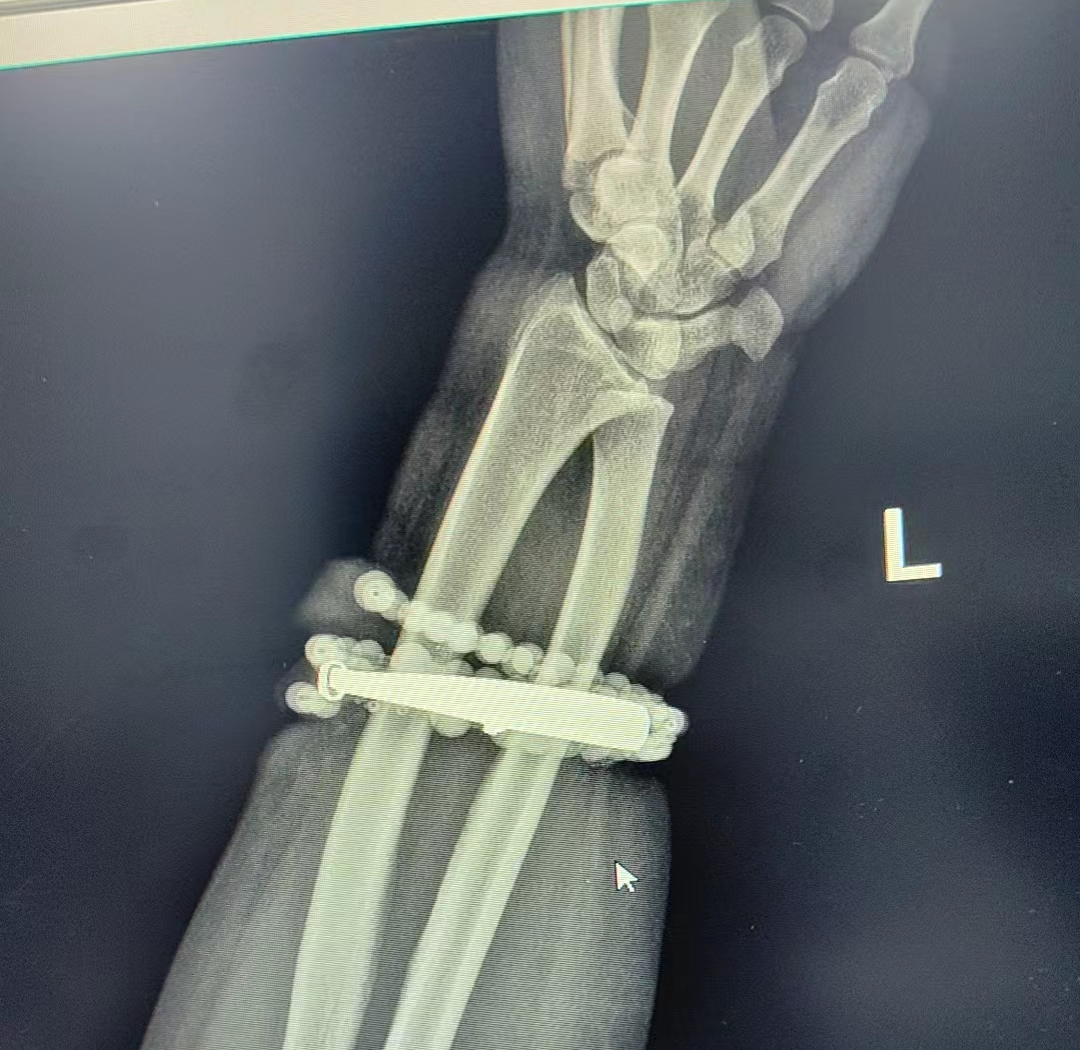

< 左右滑動查看更多 >

醫(yī)院迅速組建專業(yè)團(tuán)隊,制定手術(shù)方案。在經(jīng)過抗感染治療后,閩東醫(yī)院創(chuàng)傷骨科、手顯微外科張申申主任醫(yī)師主刀,為龔女士實施“前臂異物取出術(shù)+清創(chuàng)術(shù)”。

經(jīng)過一個多小時的精細(xì)操作,醫(yī)生們成功將手鐲和串珠從厚厚的增生組織中完整剝離出來。隨后,醫(yī)生對傷口進(jìn)行了徹底清創(chuàng)、沖洗,并放置引流條,確保感染不再復(fù)發(fā)。